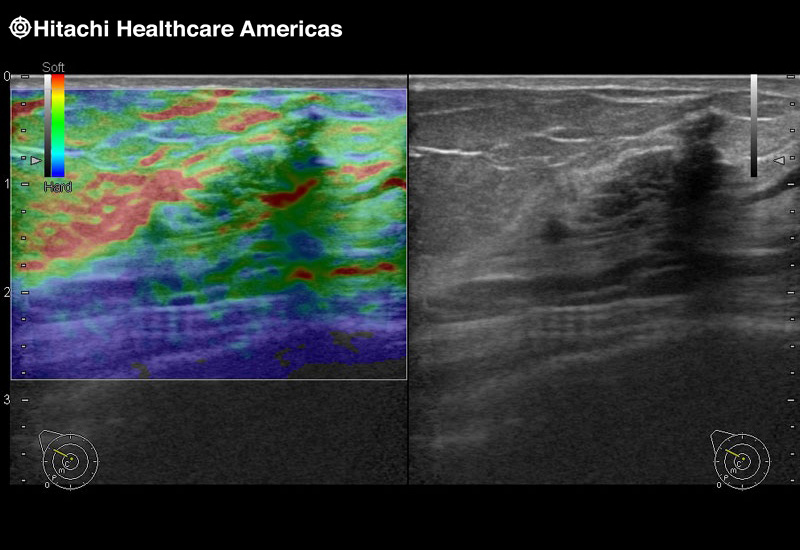

Superior guidance for all applications

Fujifilm Healthcare Americas is committed to designing tools that help surgeons navigate inside the human body and provide the necessary information to immediately make critical surgical decisions.

Fujifilm Healthcare's dedication to Surgeons provides outstanding ultrasound technology, professional support and the specialized tools necessary to best perform comprehensive real-time ultrasound imaging in Breast Surgery, General Surgery, Laparoscopic Surgery, Neurosurgery, Robotic Surgery and Surgical Oncology.

Fujifilm Healthcare’s ARIETTA Precision features state-of-the-art digital architecture and advanced imaging technologies to redefine the capabilities of surgical ultrasound.

Fujifilm Healthcare’s ARIETTA Precision features state-of-the-art digital architecture and advanced imaging technologies to redefine the capabilities of surgical ultrasound.

Imaging Clearly Defined

State-of-the-art digital architecture and advanced imaging features to redefine the capabilities of surgical ultrasound.